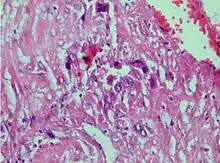

| Photomicrograph showing proliferating intermediate trophoblast with scarce cytotophoblastic and syncytiotrophoblastic elements | |

A placental site trophoblastic tumor is a monophasic neoplasm of the implantation site intermediate trophoblast, and usually a benign lesion, which comprises less than 2% of all gestational trophoblastic proliferations. Preceding conditions include molar pregnancy (5%). Compared to choriocarcinoma or invasive mole, hemorrhage is less conspicuous and serum β-HCG level is low, making early diagnosis difficult.

Immunohistochemistry: Often stains with hPL, keratin, Mel-CAM, EGFR.